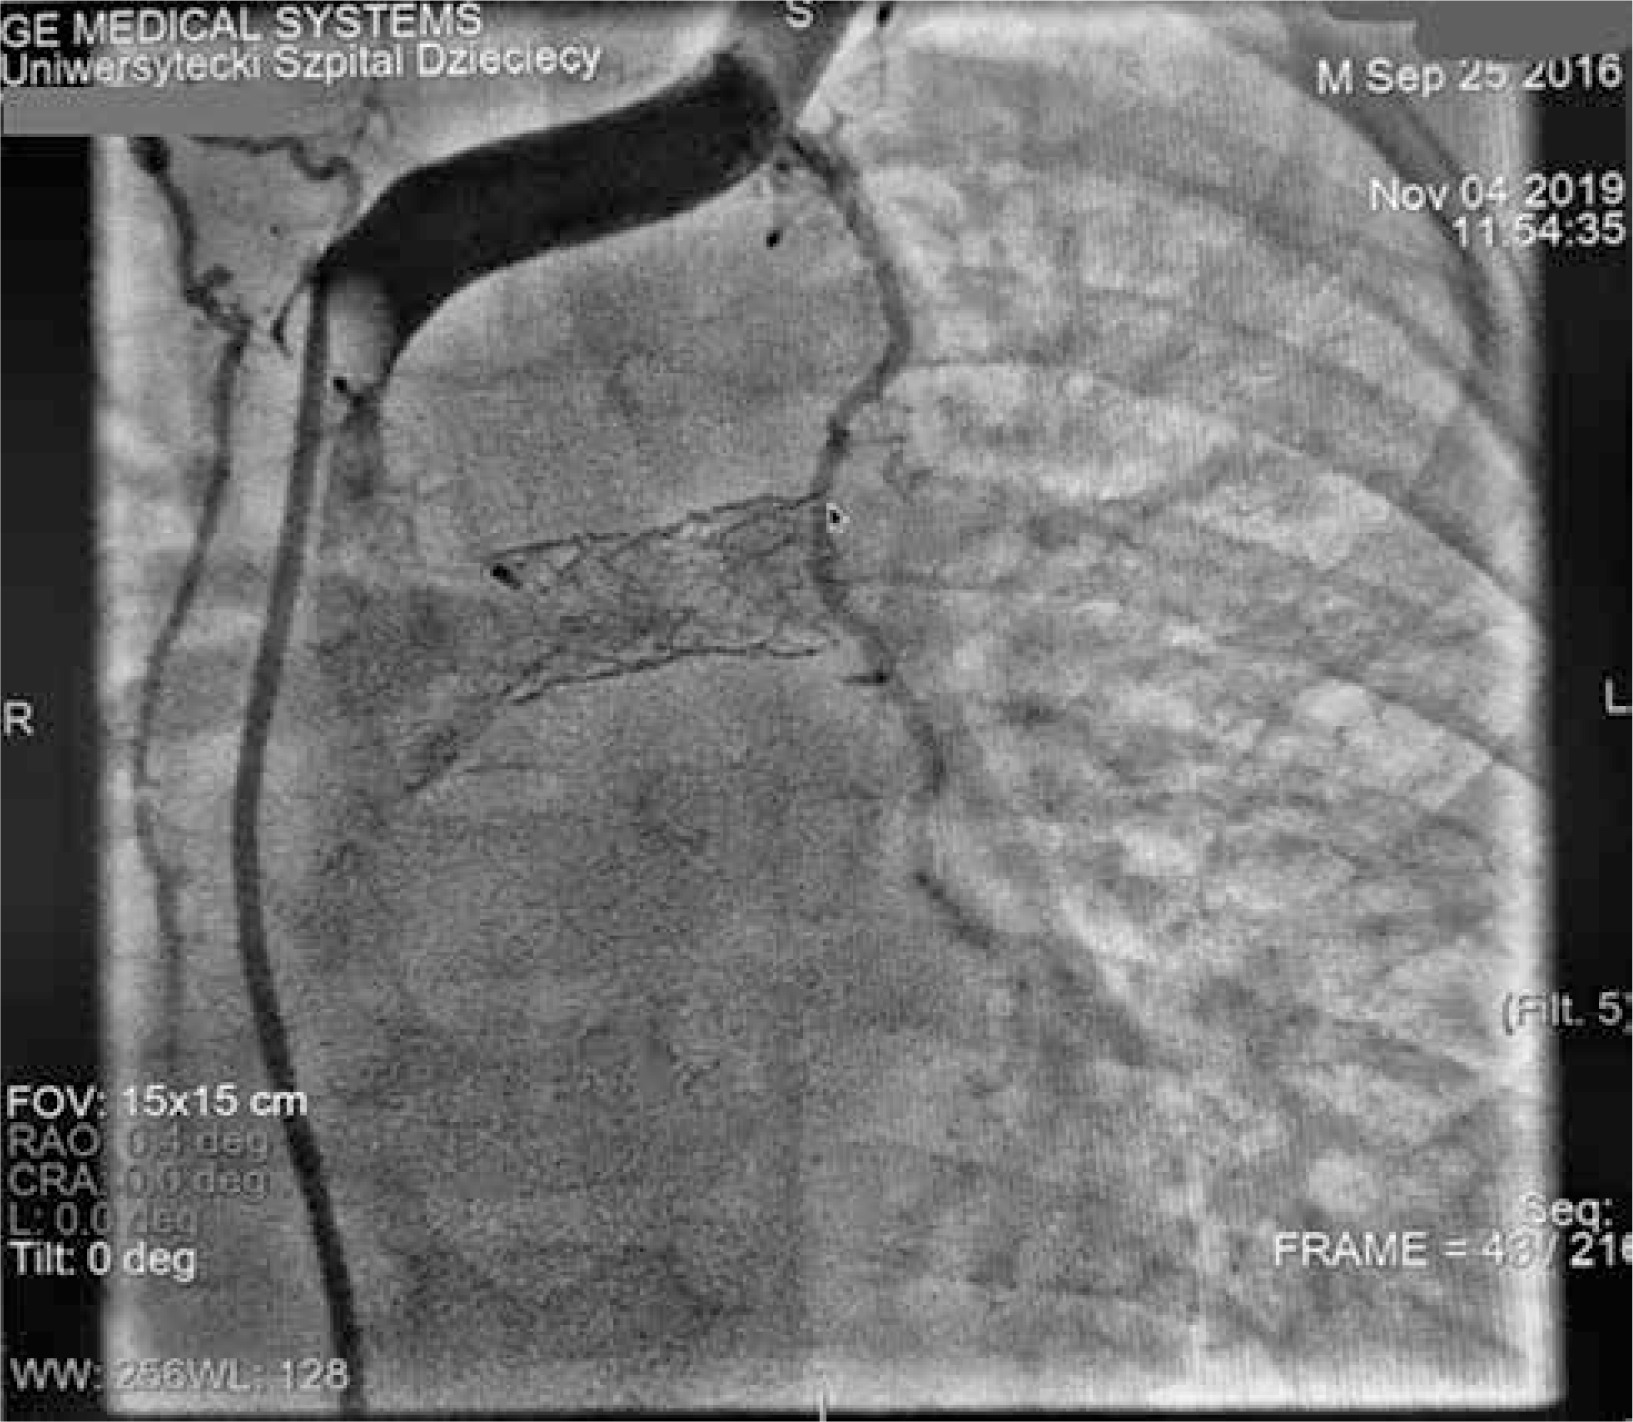

The 6-minute walk test showed reduced exercise tolerance, with a distance of 351 m and oxygen desaturation from 86% to 75%. Dynamic contrast magnetic resonance lymphangiography (DCMRL) revealed early opacification of the mesenteric lymphatic system, suggesting retrograde flow, with the absence of the cisterna chyli and cranial part of the thoracic duct. A tangled network of lymphatic structures was seen around the bronchi and trachea, indicating lymphatic abnormalities and high systemic venous pressure from the failing Fontan circulation (Figure 5).

Figure 5

Dynamic contrast magnetic resonance lymphangiography (DCMRL). A – Early opacification of the mesenteric lymphatic system, suggesting retrograde flow; B – delayed appearance of the thoracic duct and tangled network of lymphatic structures around the bronchi and trachea; C – late phase with remaining contrast indicating lymphatic abnormalities and high systemic venous pressure from the failing Fontan circulation